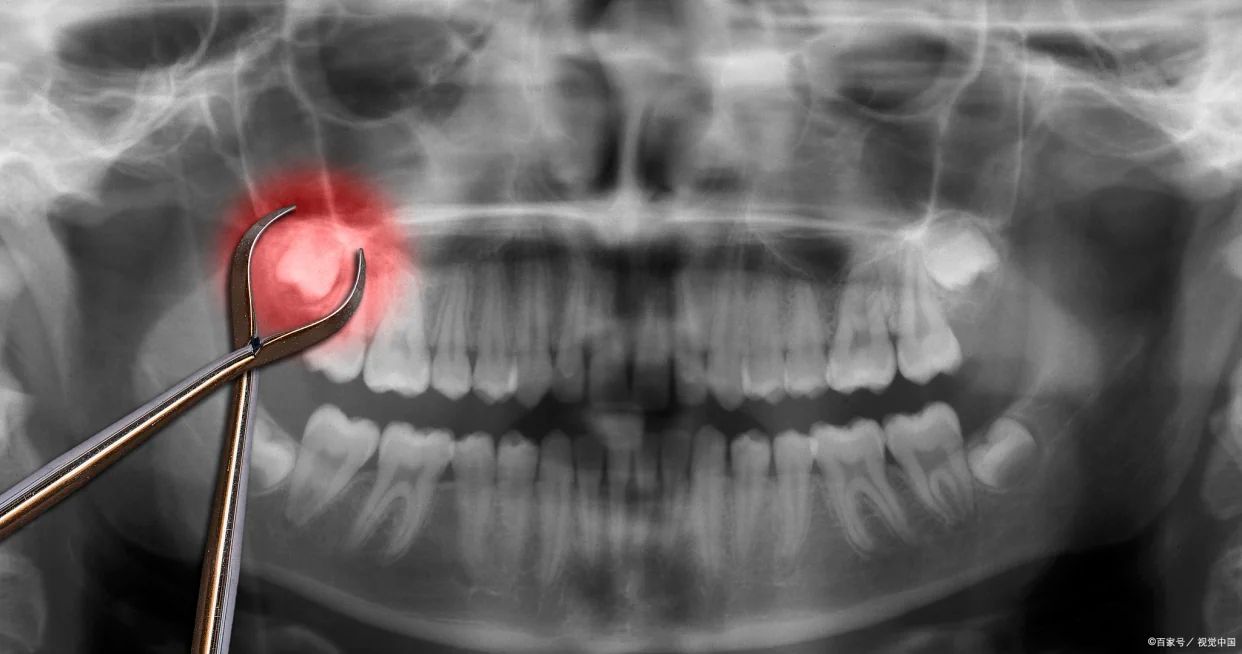

再講技術層面。近幾年,內地牙醫接受培訓同考牌制度都越來越規範,有啲醫師仲喺香港、歐美進修過。拔牙技術熟練、手勢溫柔,可以有效減少痛楚同出血風險。一啲診所仲會喺拔牙前做三維影像檢查,准確評估牙根同神經走向,從而降低術中不適。對怕痛嘅人嚟講,如果麻醉控制得宜、溝通順暢,整個過程其實幾輕松。